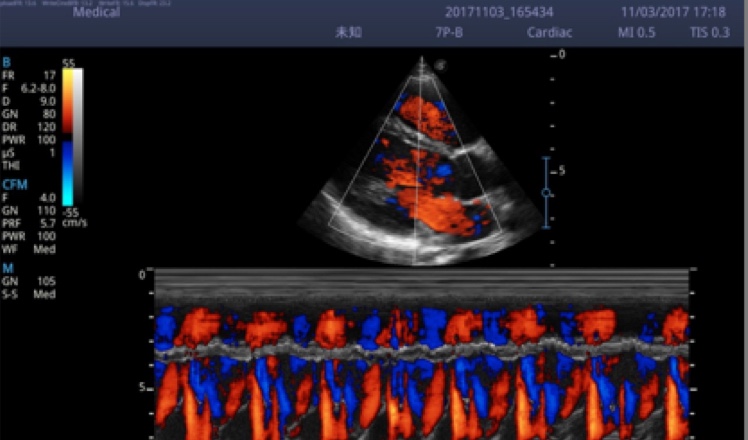

X5采用前端的超声专用芯片,将台式机大规模集成电路完美压缩在笔记本超声的精巧下,提高了系统的运算速度,加载μ-Scan微米成像、脉冲反相谐波等技术,带来优异的临床表现,清晰呈现高分辨率二维图像和层次丰富的血流图像

X5具备实时宽景成像、穿刺增强、彩色M型、组织多普勒等多种高级成像功能,全方位满足多个科室的诊断需求,整机系统向智能化跨越